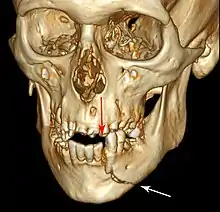

Injuries to supporting bone

This injury involves the alveolar bone and may extend beyond the alveolus.[5][6] There are five different types of alveolar fractures:

- Fracture of the maxilla: Le Fort fracture, zygomatic fracture, orbital blowout

- Fracture of the mandible

Trauma injuries involving the alveolus can be complicated as it does not happen in isolation, very often presents along with other types of tooth tissue injuries.

Signs of dentoalveolar fracture:

Investigation: Require more than one radiographic view to identify the fracture line.

Treatment: Reposition displaced teeth under local anaesthetic and stabilise the mobile segment with a splint for 4 weeks, suture any soft tissue lacerations.